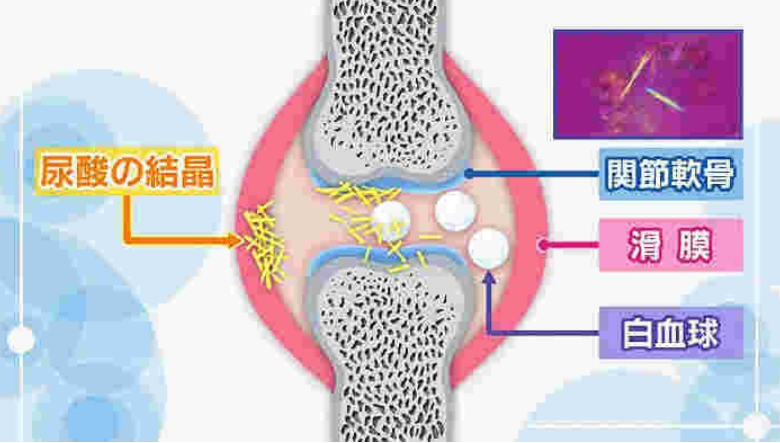

痛風は尿酸が体の中にたまり、それが結晶になって激しい関節炎を伴う症状になる病気です。医学研究が進み、良い薬も開発されたため正しい治療を受ければ全く健康な生活が送れます。しかし、放置すると激しい関節の痛みを繰り返したり、体のあちこちに結節が出来たり、腎臓が悪くなったりする重大な病気でもあります。

引用:tufu.or.jp

痛風の原因はプリン体の過剰摂取で、ビールやたらこなどのプリン体の含有量が多い食べ物を過度に体内に取り込む事で、尿酸が関節に沈着し、尿酸値が高くなることで痛風関節炎は頻発します。